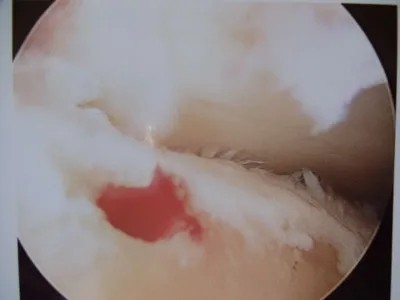

Pic after microfracture and debridement of above OCD.